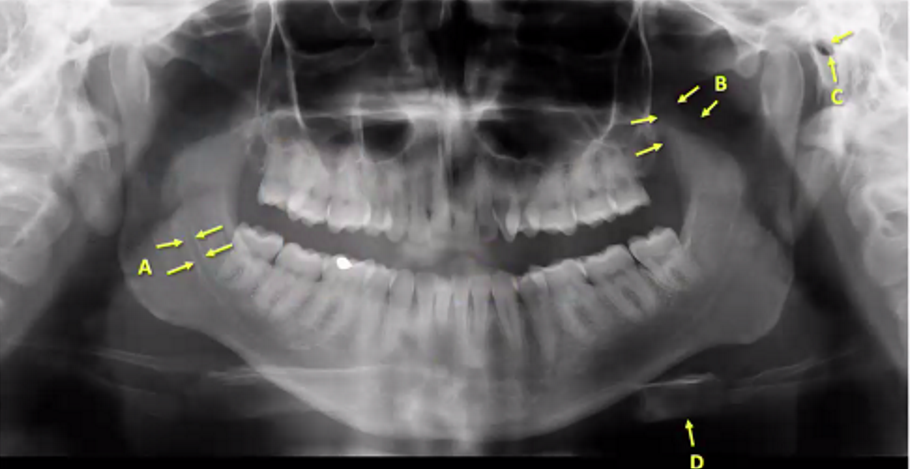

A

medial wall of maxillary sinus (right)

B

zygomatic process/buttress

C

maxillary tuberosity

D

mental foramen